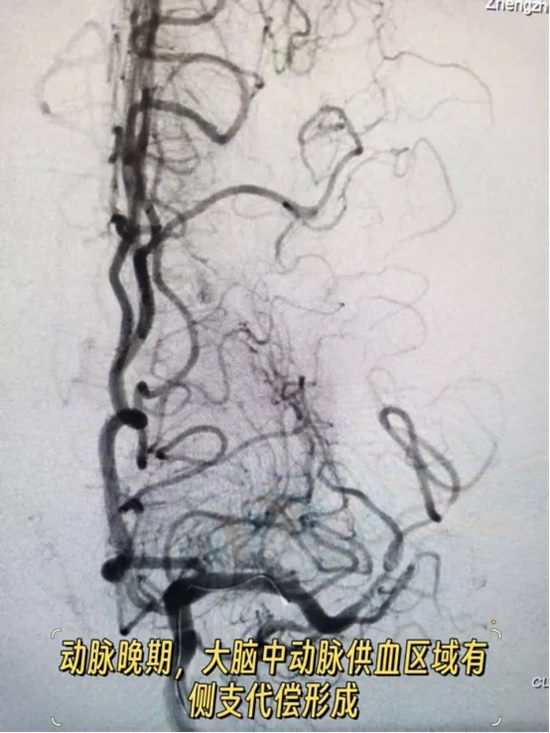

他们发现:大脑前动脉向大脑中动脉供血区域有代偿。

这意味着什么

意味着:大脑中动脉可能并非急性闭塞。此时即便不开通,凭借侧支循环的代偿作用,也不会造成大面积脑梗死,患者的生命安全已基本得到保障。

反之,若强行继续取栓,不仅难以达到预期效果,还可能导致脑出血等致命并发症——得不偿失。

经过审慎评估和科学研判,马建主任与周少龙副主任果断决定:终止手术。